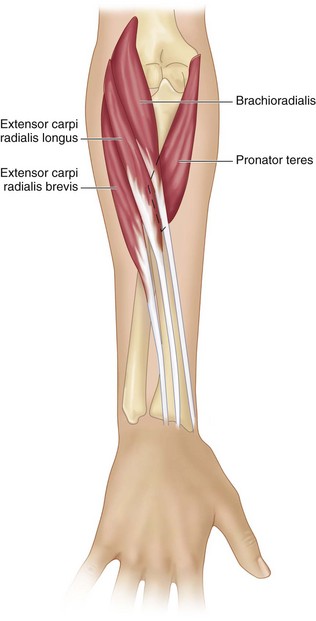

Анатомия и функции мышцы brachioradialis